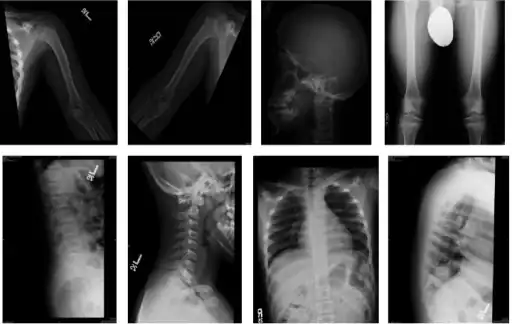

The diagnosis of this condition can be done via X-rays (with lack of normal distance L1 to L5),[8] and additionally genetic testing is available to ascertain hypochondroplasia.[9]

-

Skeletal survey in favor of hypochondroplasia -